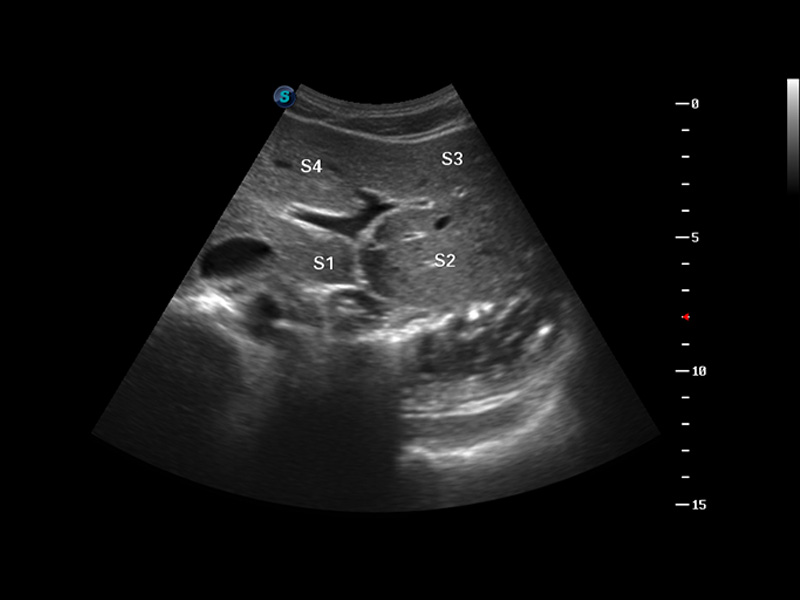

μ-Scan微米成像

谐波成像

空间复合成像